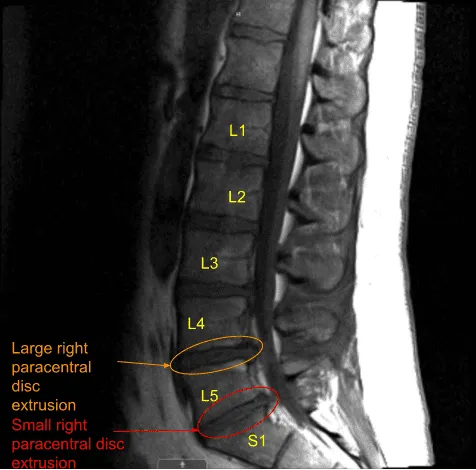

The patient had good relief after the surgery which was followed by recurrence of the pain in two weeks. This was associated with tingling and numbness along with foot drop on the right side. A repeat MRI was done which showed a re-herniation of disc on the right L4-L5.

MRI and CT of Lumbar spine were done which showed degenerative disc disease L4-5 and L5-S1 with re-herniation at L4-5.